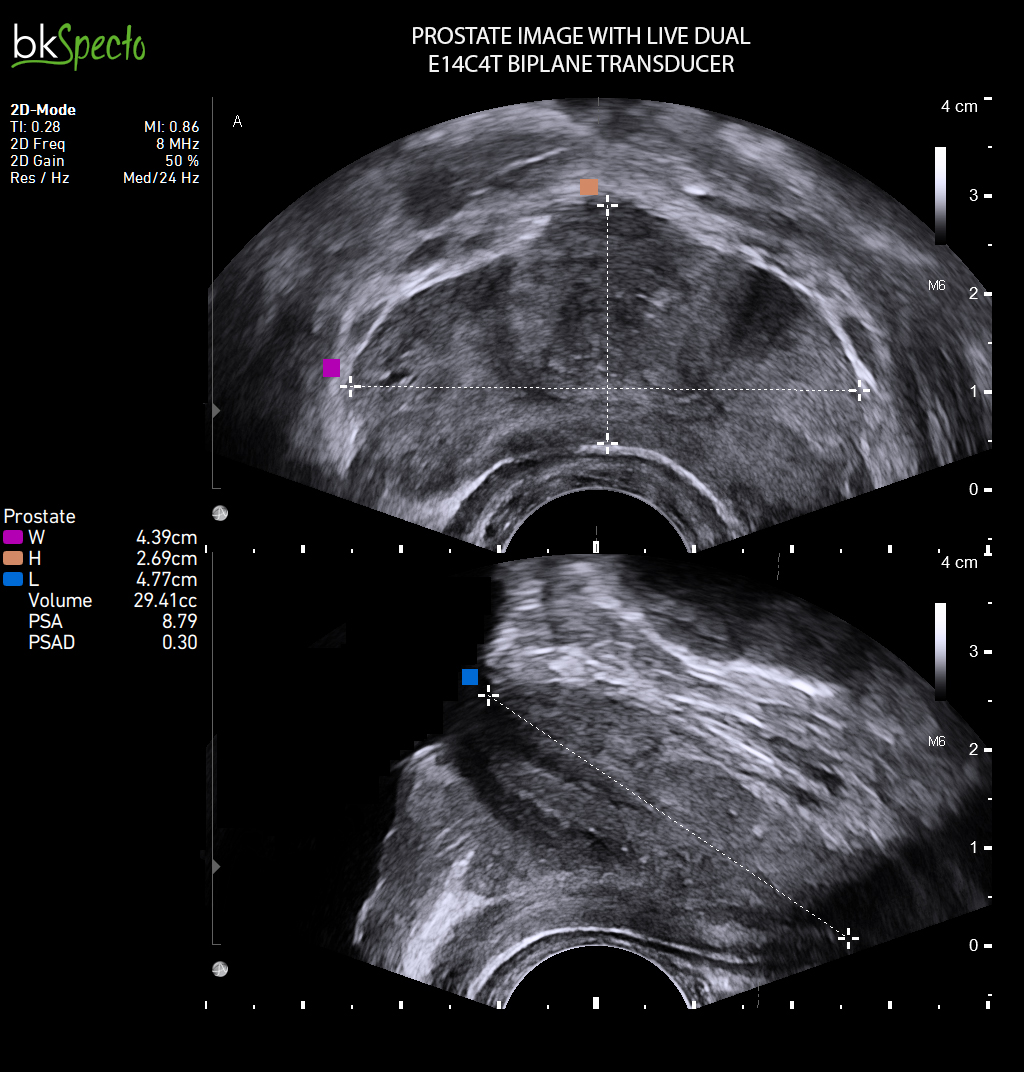

BkSpecto là hệ thống siêu âm chuyên về các thủ thuật can thiệp cho các chuyên khoa: Tiết niệu, gây mê, cơ, tuyến vú, tuyến giáp, sản phụ khoa và hậu môn trực tràng.

- Là thương hiệu đầu tiên và hàng đầu thế giới với hơn 40 năm chuyên về sinh thiết và dẫn hướng điều trị qua hình ảnh siêu âm. BkSpecto được thiết kế đặc biệt cho các ký thuật: Sinh thiết u xơ tiề liệt tuyến, sinh thiết qua đồng bộ hình ảnh siêu âm và MRI, điều trị u bằng đặt hạt phóng xạ, thăm khám dương vật/tinh hoàn, thăm khám thận/bàng quang, tán sỏi thận qua da PCNL.

- Với phần mềm độc quyền MIM và tính năng bkFusion chẩn đoán, sinh thiết và điều trị chính xác vị trí u xơ tiền liệt tuyến cực kỳ nhanh chóng